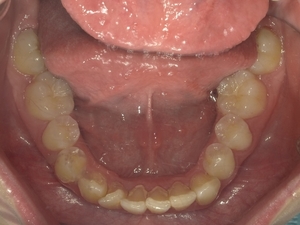

ガタガタとした歯並びや八重歯(叢生)CASE72